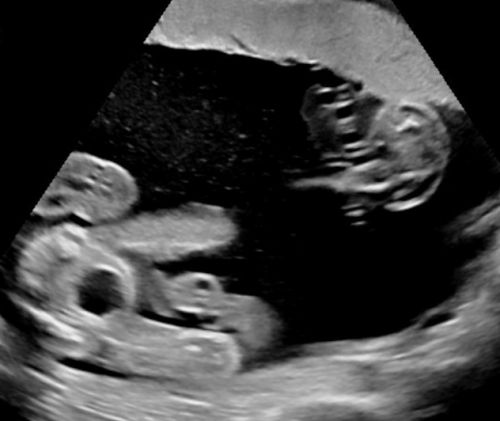

Sono-Online - fetale Fehlbildungen: "Mehrlinge"

Sonoanatomie, Biometrie, Hinweiszeichen & Diagnose von Entwicklungsstörungen, Kasuistiken, ausreichend Zeit für Diskussionen, Fallbeispiele aus der Praxis (Quiz)